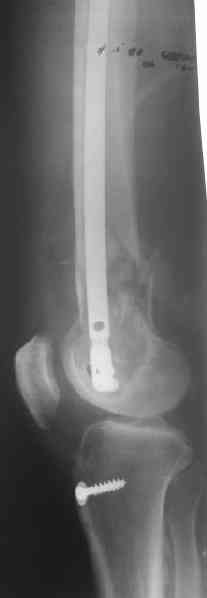

It appears to me as if someone has already tried to "Mold" or contour this plate - there seems to be an extra angle in it. This plate should not be contoured, since the shape of it (the 95 degree angle) is what allows it to be used , when inserted correctly, to re-establish the relationship between the joint and shaft axes.

I think the primary problem is "simply" a translational one and not a major angular deformity. I wonder if the shortening is more related to contracture than loss of bone. I would obtain long alignment films (hip- knee-ankle), and perhaps a scanogram, or at least separate bilateral femur films, to try and sort these issues out.

I think I would favor treatment to healing in this position, with aggressive PT and then re-evaluate the extent of disability. Nutritional and medical optimization and a bone stimulator may be worth considering. The presence of a cerclage wire in an area of comminution is often forensic evidence of bone murder. I am not optimistic that a retrograde nail would lead to secure healing and would worry about taking it all apart at this stage.